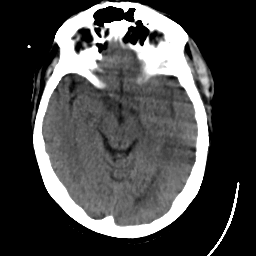

Meningioma: Roentgen-ray CT #1 -- Slice #8

[Home][Help][Clinical] Slice 8